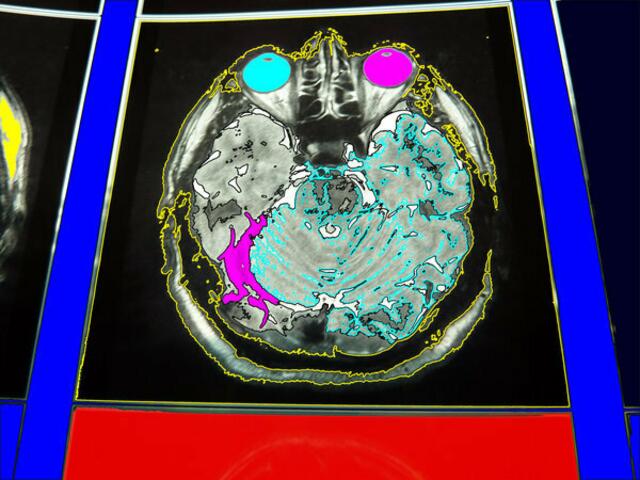

Für die Entstehung der Symptome der Parkinson-Krankheit sind die Nervenzellen der Substantia nigra (schwarze Substanz) von besonderer Bedeutung. ... Mittelhirn-a&s-p-malerei. wh

Für die Entstehung der Symptome der Parkinson-Krankheit sind die Nervenzellen der Substantia nigra (schwarze Substanz) von besonderer Bedeutung. Mittelhirn-a&s-p-malerei. wh 2-5-11.